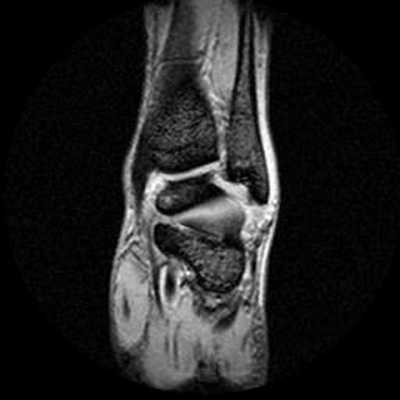

МРТ голеностопного сустава в корональной плоскости.

Отмечается поперечный стресс-перелом дистальных отделов малоберцовой кости.